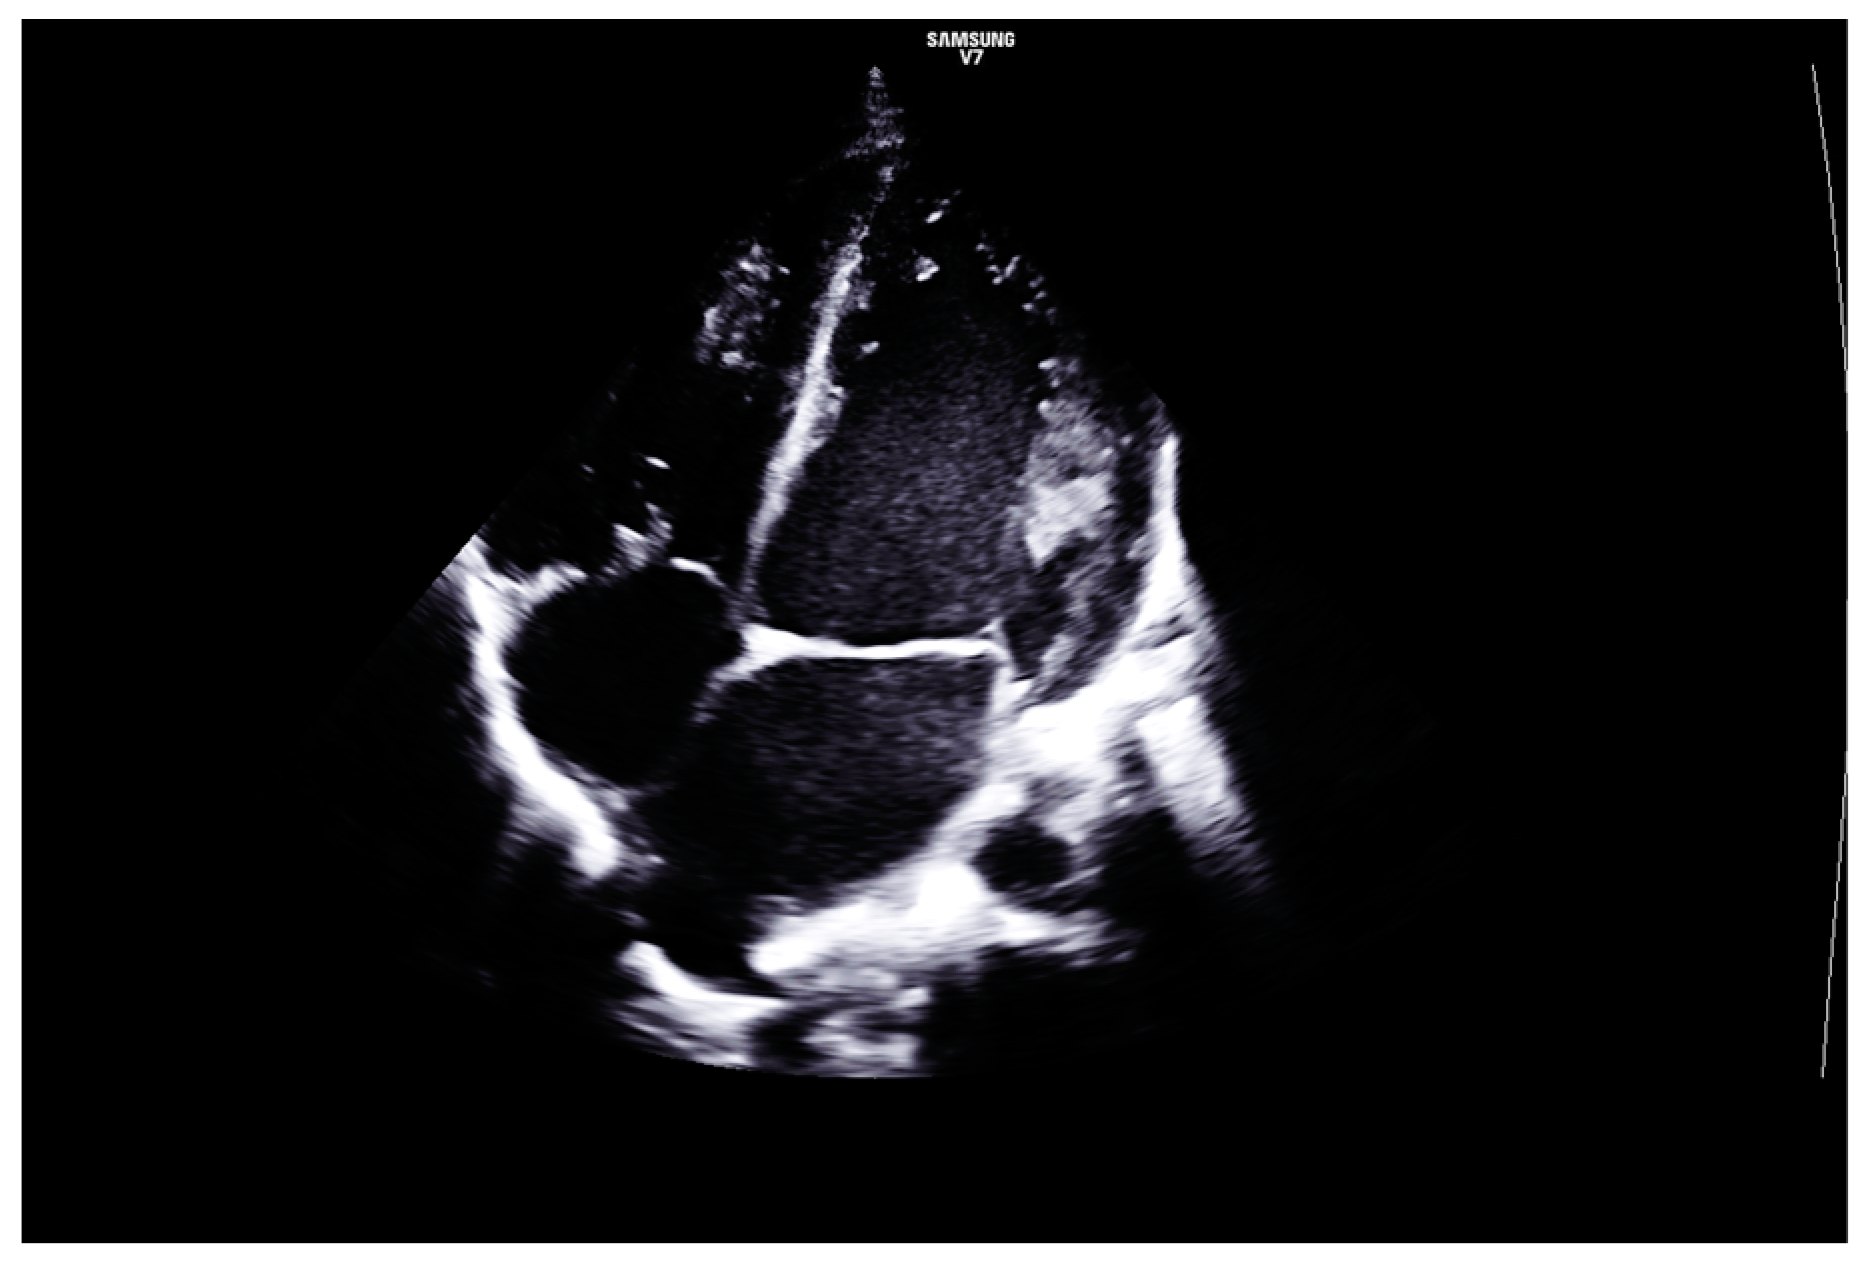

2. Case Report